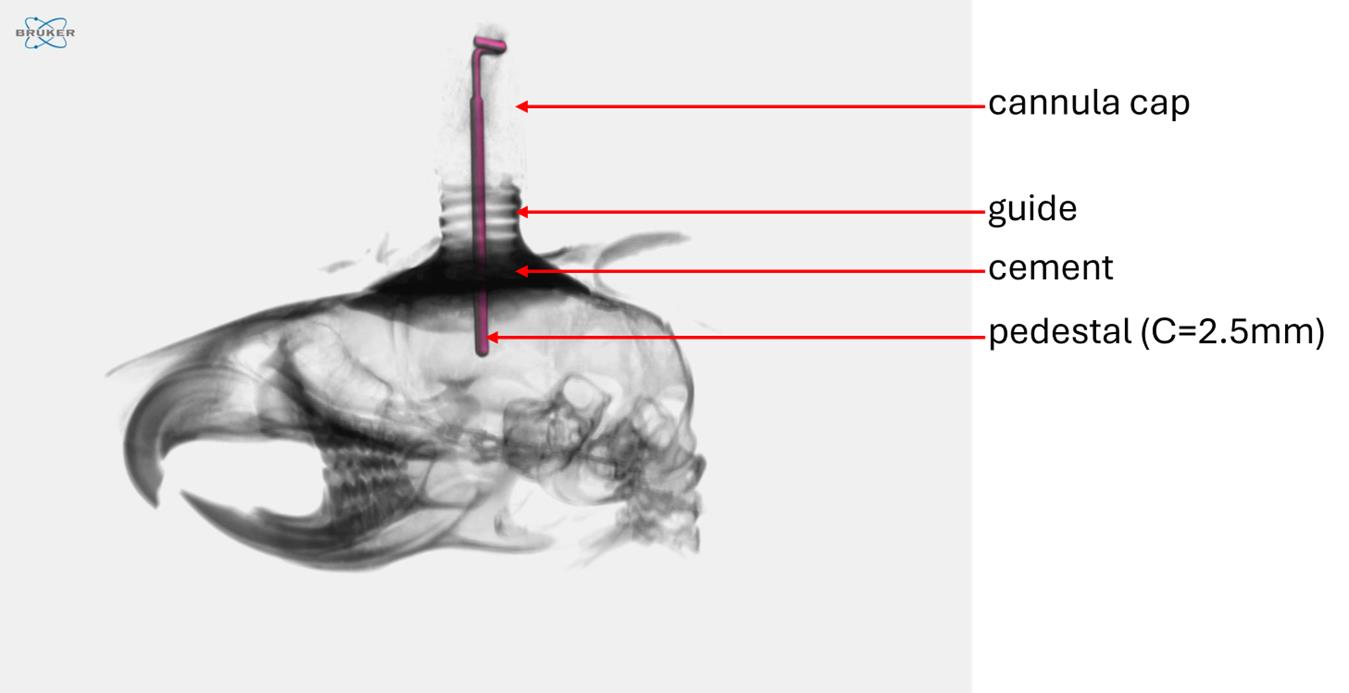

1. Guide cannula-single/O.D.0. 48 mm-26G/pedestal 6 mm/3.5, autoclave up to 121 °C (C = 2.5MM, RWD®, catalog number: 62003)

2. The choice of material and the design of the intracerebral cannulas were critical aspects of the experimental setup. Plastic cannulas were preferred over metal ones due to their lighter weight, which helped minimize mechanical stress on the animal. Additionally, plastic is compatible with imaging techniques such as micro-CT or X-ray, as it does not generate artifacts. The selected plastic also needs to withstand effective sterilization procedures; an autoclavable material (up to 121 °C) was therefore deemed optimal. Cannulas from RWD® fulfilled these requirements, and the option for custom manufacturing was a significant advantage. The chosen model featured a pedestal length of 2.5 mm and an internal diameter corresponding to a 26G needle, aligning with the typical depth used for tumor cell inoculation in the murine striatal injection model [6]. The cannula cap included a metal tip designed to prevent guide obstruction. This tip extended 0.5 mm beyond the guide once the cap was in place, thus penetrating the intracerebral space by 0.5 mm when closed.

6. Cannula implantation and fixation using G-Cem One cement were validated on several cadavers of 6–8-week-old Balb/cJ mice. To assess intracerebral placement, the heads of two mice were excised and imaged using X-ray micro-computed tomography (Figure 11).